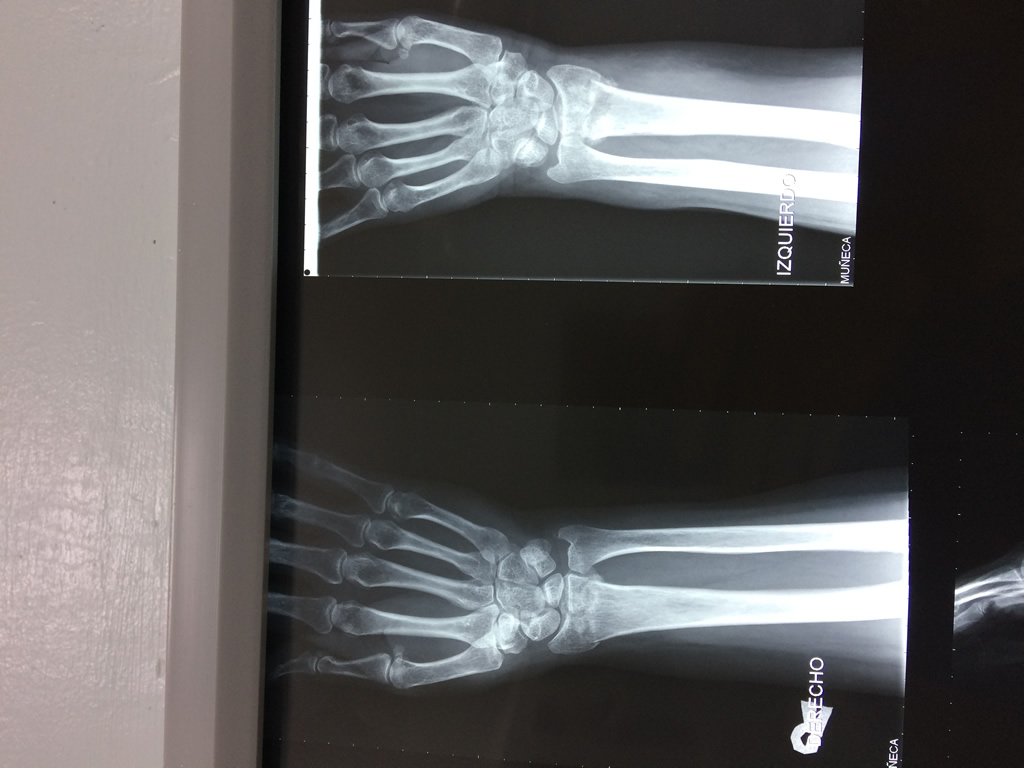

Cirugía de Fémur - Cirugías de Muñecas y Manos

Los procedimientos más comunes en cirugía de la mano son aquellos destinados a reparar traumatismos, incluyendo lesiones de tendones, nervios, vasos sanguíneos, y articulaciones; huesos fracturados; y quemaduras, cortes, y otros daños de la piel.